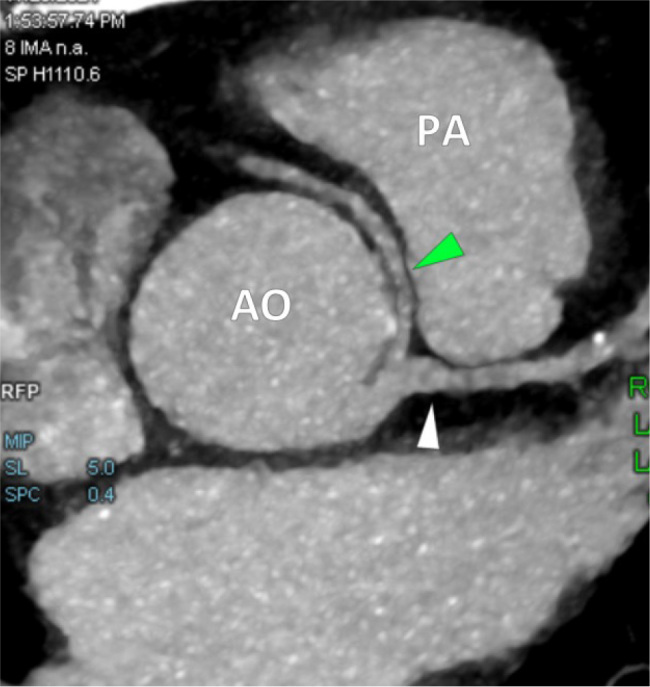

冠状动脉起源异常是一种罕见的先天性疾病,可表现为非特异性胸痛或呼吸短促或无症状。早期识别是至关重要的,因为某些变异与心脏性猝死的高风险有关。在此,我们报告一例53岁女性高血压,甲状腺功能减退,肥胖(II级)和间歇性胸痛放射到左臂两年的病史。心脏科检查包括心电图、心脏酶、超声心动图和CT冠状动脉造影显示右冠状动脉(RCA)起源于左冠状动脉主干(LMCA),但血流动力学上没有明显的狭窄。本病例强调了先进成像技术在评估非典型胸痛中的重要性,它可以揭示冠状动脉的关键先天性异常。虽然该异常与本例患者的缺血无关,但其识别对于适当的管理和风险分层至关重要。学习要点:先进的成像技术在评估非典型胸痛时很重要,它可以显示冠状动脉的关键先天性异常。CT冠状动脉造影仍然是诊断和风险评估的重要工具。尽管本例中右冠状动脉与缺血无关,但持续监测和心血管危险因素管理对于长期预后至关重要。

Anomalous origin of the coronary arteries is a rare congenital condition that can present as non-specific chest pain or shortness of breath or remain asymptomatic. Early identification is critical as certain variants are linked with a high risk of sudden cardiac death. Here, we report the case of a 53-year-old female with hypertension, hypothyroidism, obesity (class II) and a history of intermittent chest pain radiating to the left arm for two years. A cardiology workup including ECG, cardiac enzymes, echocardiography and CT coronary angiography revealed an anomalous origin of the right coronary artery (RCA) arising from the left main coronary artery (LMCA) with no haemodynamically significant narrowing. This case highlights the significance of advanced imaging techniques in evaluating atypical chest pain, which can reveal critical congenital anomalies of the coronary arteries. Although this anomaly was not associated with ischaemia in our patient, its recognition is vital for appropriate management and risk stratification.

Learning points: Advanced imaging techniques are important in evaluating atypical chest pain, which can reveal critical congenital anomalies of the coronary arteries.CT coronary angiography remains an essential tool for diagnosis and risk assessment.Although the right coronary artery was not associated with ischaemia in this case, continued monitoring and cardiovascular risk factor management are essential for long-term prognosis.